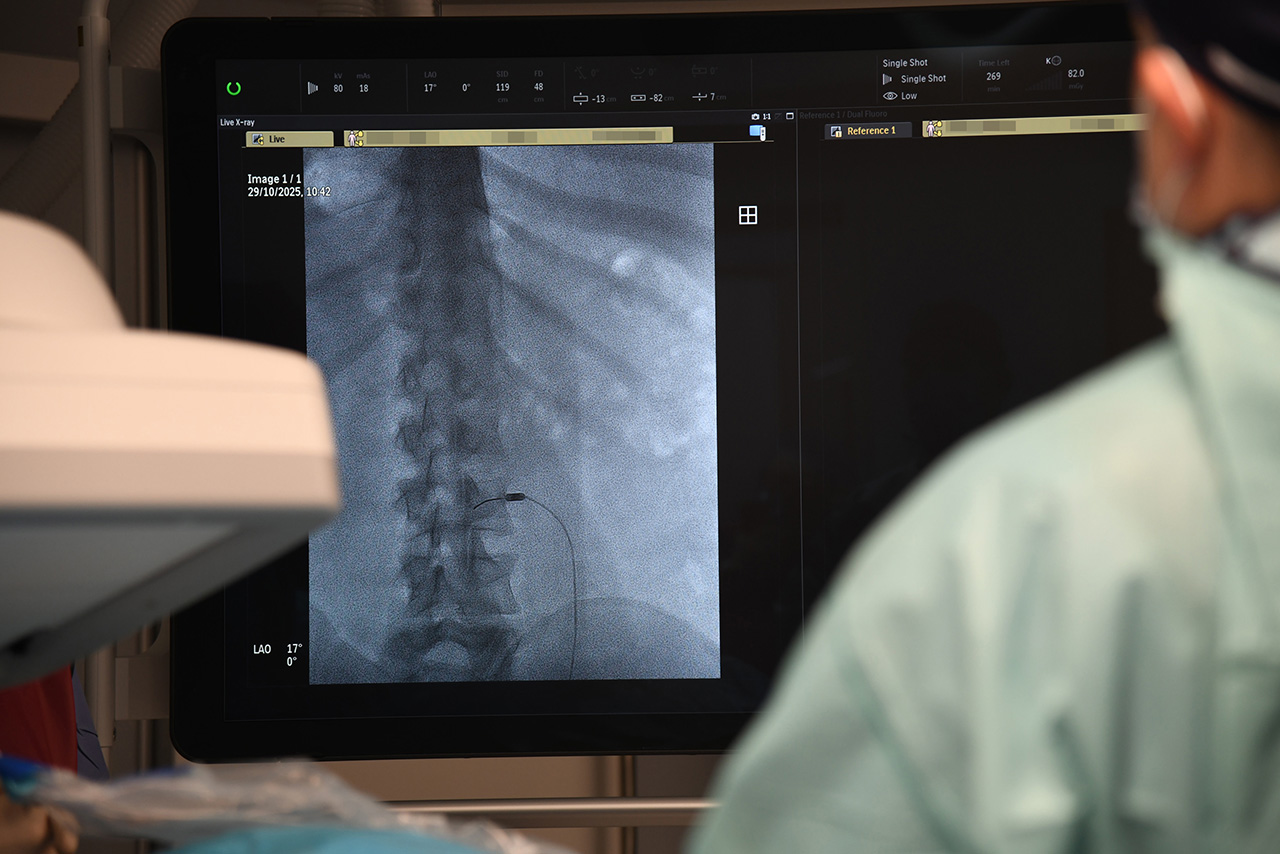

Na czym polega zabieg? Nazwa termolezja, oznacza niszczenie temperaturą. Stosowana jest np. u pacjentów z dolegliwościami bólowymi, które wynikają z uszkodzenia nerwu lub nieprawidłowych impulsów tworzonych w obrębie receptorów, czyli struktur, które odbierają bodźce bólowe. – Na przykład, mamy pacjenta z bólem, tak zwanym, rzekomo-korzeniowym. Nie ma dyskopatii, natomiast bardzo go bolą plecy. Z czego może wynikać ten ból? Z przeciążenia stawów międzykręgowych. Co możemy wtedy zrobić? Zniszczyć unerwienie tych stawów. Robimy to wbijając igłę, pod kontrolą prześwietlenia rentgenowskiego, bo jest to metoda wymagająca precyzji. Do igły wprowadzamy emiter prądów wysokiej częstotliwości i nagrzewamy tkanki do temperatury – w tym konkretnym przypadku – 85 stopni Celsjusza. Nagrzewamy miejscowo tylko tę strukturę, która nas interesuje, bo pole rażenia tej elektrody jest niewielkie – mówi Rafał Muchowski, neurochirurg z Oddziału Neurochirurgii Wojewódzkiego Szpitala Specjalistycznego w Słupsku.

Wysoki poziom wykonywania termolezji w słupskim szpitalu jest możliwy dzięki używanemu sprzętowi wysokiej klasy, np. nowoczesnemu angiografowi zakupionemu przez szpital na początku 2025 r.